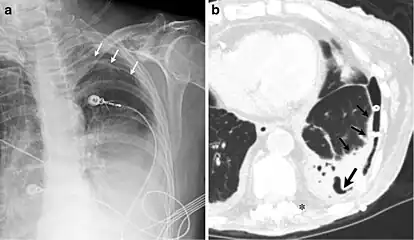

A fibrothorax can typically be diagnosed by taking an appropriate medical history in combination with the use of appropriate imaging techniques such as a plain chest X-ray or CT scan.[3] These imaging techniques can detect fibrothorax and pleural thickening that surround the lungs.[7] The presence of a thickened peel with or without calcification are common features of fibrothorax when imaged.[3] CT scans can more readily differentiate whether pleural thickening is due to extra fat deposition or true pleural thickening than X-rays.[3]

If a fibrothorax is severe, the thickening may restrict the lung on the affected side causing a loss of lung volume.[7] Additionally, the mediastinum may be physically shifted toward the affected side.[3] A reduction in the size of one side of the chest (hemithorax) on an X-ray or CT scan of the chest suggests chronic scarring.[6] Signs of the underlying disease causing the fibrothorax are also occasionally seen on the X-ray.[6] A CT scan may show features similar to those seen on a plain X-ray.[7] Lung function testing typically demonstrates findings consistent with restrictive lung disease.[6]

CXR of an individual affected by fibrothorax (consequence of tuberculosis)

Extensive left-sided fibrothorax